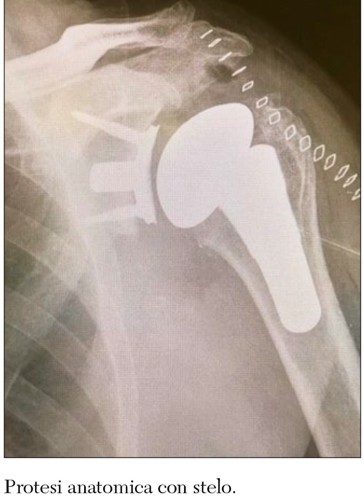

La protesi totale anatomica ha l’obiettivo di riprodurre l’anatomia della spalla normale e il requisito essenziale per il suo utilizzo è che la cuffia dei rotatori sia integra e funzionante. In questo tipo di protesi la testa omerale si sostituisce con una cupola metallica e la superficie glenoidea si sostituisce con una componente concava in polietilene.

Gli ancoraggi a press fit riguardano le protesi con steli corti o protesi senza stelo da utilizzare nei pazienti più giovani in quanto il tessuto osseo è più resistente e normotrofico.

La protesi tradizionale con stelo rimane ancora un presidio necessario nei casi di frattura pluriframmentata della spalla e dove si riscontrano importanti difetti ossei omerali. Questi possono presentarsi nei pazienti affetti da mancata saldatura di frattura e nei casi più complessi come in quelli di resezioni tumorali.